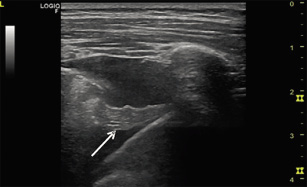

Cuando en una neumonía persiste la fiebre, la tos pleurítica o la dificultad respiratoria pese a antibiótico, se debe sospechar derrame pleural. Dado que la inserción del diafragma es más caudal a nivel posterior del tórax, el examen debe centrarse en los campos posteriores y laterales, más declives con el paciente sentado o en brazos de la madre (Fig. 9).

Figura 9. A. Signo del cuadrado (modo B). B. Signo del sinusoide (modo M).

• Patrones ecográficos:

– Espacio anecoico entre pleura visceral y parietal.

– Signo del cuadrado (modo B): colección anecoica delimitada lateralmente por la sombra acústica de las costillas. El límite inferior es la pleura visceral (hiperecoica) y el límite superior es la parietal.

– Signo del sinusoide (modo M): línea ondulante de la pleura visceral durante la respiración.

– Si hay septos/loculaciones, pueden sugerir empiema.

– Podemos estimar el volumen del derrame pleural; la más utilizada es la fórmula de Balik, que calcula el volumen (ml) como: 20 × distancia (mm) entre la pleura visceral y la parietal, medida en la línea axilar posterior al final de la espiración. Esta fórmula, aunque desarrollada inicialmente en adultos, ha mostrado buena correlación en población pediátrica, sobre todo para el seguimiento evolutivo del derrame(20-21).